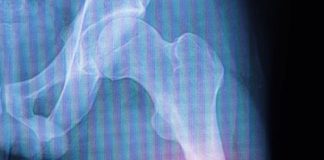

Femur Şaft Kırıkları

Femur şaft kırıkları, femur kemiğinin orta kısmında meydana gelen ciddi yaralanmalardır. Bu tür kırıklar genellikle motorlu araç kazaları veya düşme gibi yüksek enerjili travmalar...